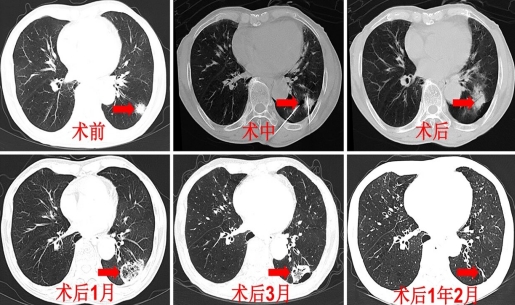

微波消融广泛应用于肺部良性结节和恶性肿瘤的治疗。对于肺部结节、早期肺癌、转移性肺癌以及其他肺部恶性肿瘤,微波消融可作为一种重要的治疗手段。此外,对于一些肺部良性肿瘤,如支气管肺泡瘤等,微波消融也能起到一定的治疗效果[16]。微波消融具有较高的安全性和较少的并发症,可以达到治疗肺结节的目的。同时具有创伤小、近期疗效确切、对患者伤害小等优点。目前,研究发现微波消融也可作为一种治疗肺磨玻璃结节的新方案,尤其适合于心肺功能较差、身体状况较差的老年患者[17]。

随着人民生活水平及体检意识的提高,GGN的检出率明显升高,因其与肺腺癌具有密切的相关性而备受人们关注。老年GGN患者因多伴有基础疾病,多数不适合手术治疗,或是磨玻璃结节性质不明,因此MWA更适合这类人群。临床医师需充分了解 GGN 的生长特点,对其进行正确随访和及时处理,进而可以有效降低肺癌死亡率的同时避免过度诊治。微波消融具有较高的安全性和较少的并发症,可以达到治疗肺结节的目的。同时具有创伤小、近期疗效确切、对患者伤害小等优点。微波消融可作为一种治疗肺结节的新方案,尤其适合于心肺功能较差、身体状况较差的老年患者。降低肺癌死亡率的同时避免过度诊治。微波消融近几年临床应用广泛,其是否可以替代手术治疗,需要临床进一步研究。